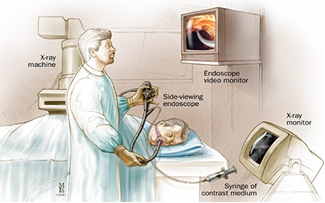

6.5 ERCP (Endoscopische Retrograde Cholangio Pancreaticografie)

Tijdens een ERCP wordt met een endoscoop in het lichaam gekeken. De endoscoop is een dunne, flexibele bestuurbare slang met aan het einde een lampje en een camera. De endoscoop wordt via de mond in de slokdarm en de maag tot aan het begin van de dunne darm ingebracht. Daar zit de gezamenlijke uitgang van de galwegen en de alvleesklier. Via de endoscoop kunnen verschillende handelingen worden uitgevoerd.

Tijdens een ERCP wordt met een endoscoop in het lichaam gekeken. De endoscoop is een dunne, flexibele bestuurbare slang met aan het einde een lampje en een camera. De endoscoop wordt via de mond in de slokdarm en de maag tot aan het begin van de dunne darm ingebracht. Daar zit de gezamenlijke uitgang van de galwegen en de alvleesklier. Via de endoscoop kunnen verschillende handelingen worden uitgevoerd.

Ten eerste kan met een endoscoop de binnenkant van de darm worden bekeken.

Door de endoscoop kan ook een contrastvloeistof in de galweg worden gespoten om een duidelijker beeld te krijgen.

Verder kunnen door de endoscoop ook cellen worden weggehaald. Hiervoor gebruikt de arts een klein borsteltje. De cellen kunnen dan worden onderzocht onder de microscoop.

Tot slot is het ook mogelijk om met de endoscoop een buisje (stent) in de galwegen te plaatsen, als bijvoorbeeld de tumor de galgang dichtdrukt. Zo kan de gal weer naar de dunne darm stromen en verdwijnen klachten zoals geelzucht.

Figuur 9: Bron: Hopkinsmedicine.org

Tijdens de behandeling word u in diepe slaap gebracht.

Verdere informatie vindt u in de Amsterdam UMC-patiëntenfolder: ERCP: een onderzoek van de galwegen.